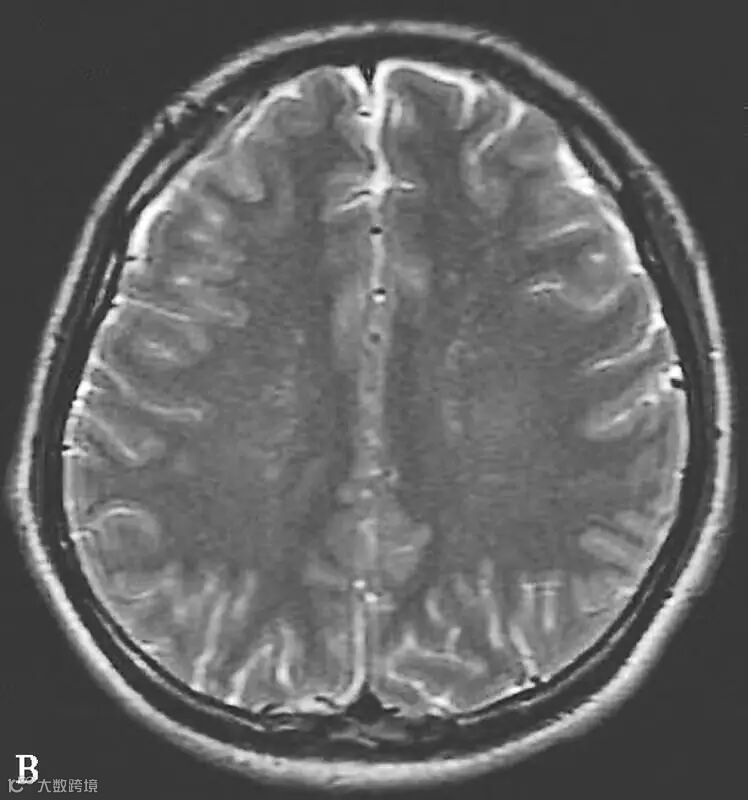

图6-11-2 弥漫性轴索损伤

男,36岁,外伤后2天。A~J(A、B.T2WI,C、D.T1WI,E、F.T2WI-FLAIR,G、H.DWI,I、J.ADC图):双侧额叶、半卵圆中心及胼胝体压部可见多发斑点状等T1稍长T2信号,边缘不清,FLAIR及DWI呈高信号,ADC图病灶信号减低 。